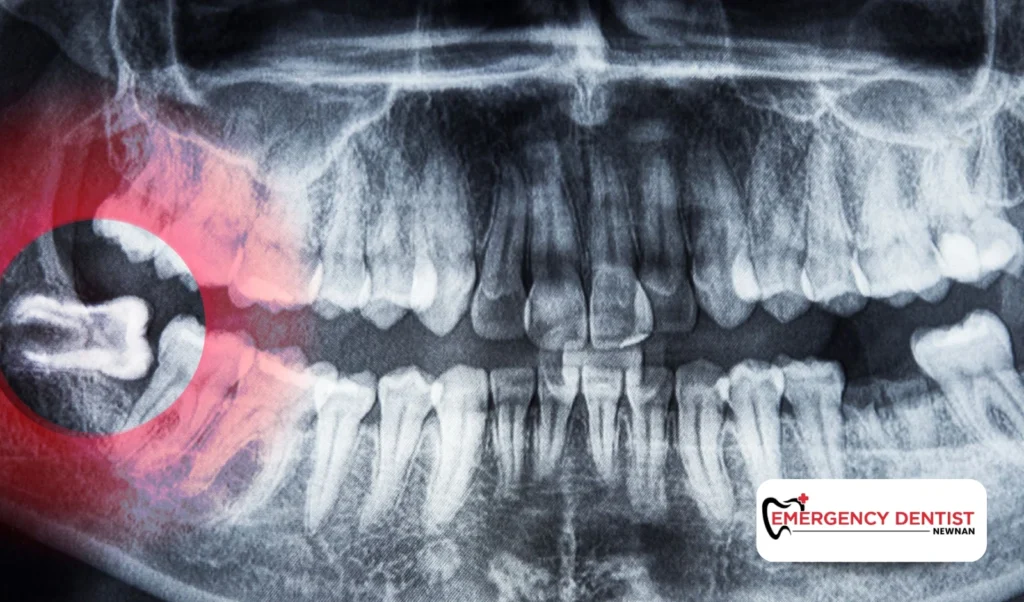

• Take diagnostic X-rays

• Evaluate tooth position

• Determine the type of extraction

This personalized evaluation provides a clearer answer to questions like how much does a wisdom tooth extraction cost and what the average cost of a wisdom tooth removal may look like in your specific case.